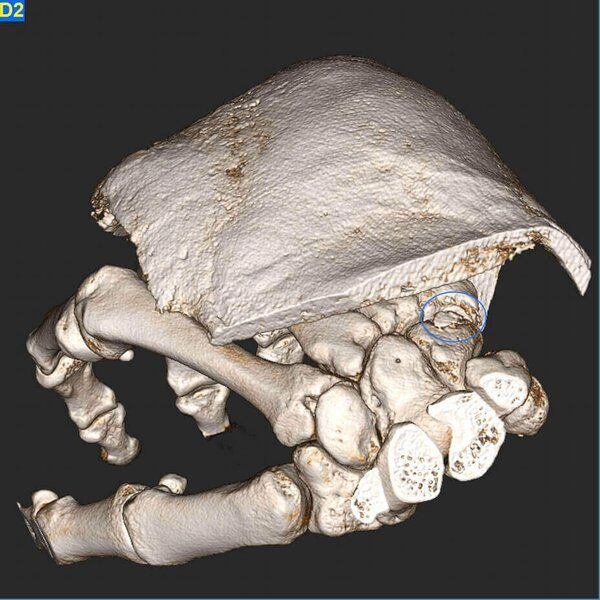

Fractura de escafoides con material de osteosíntesis.